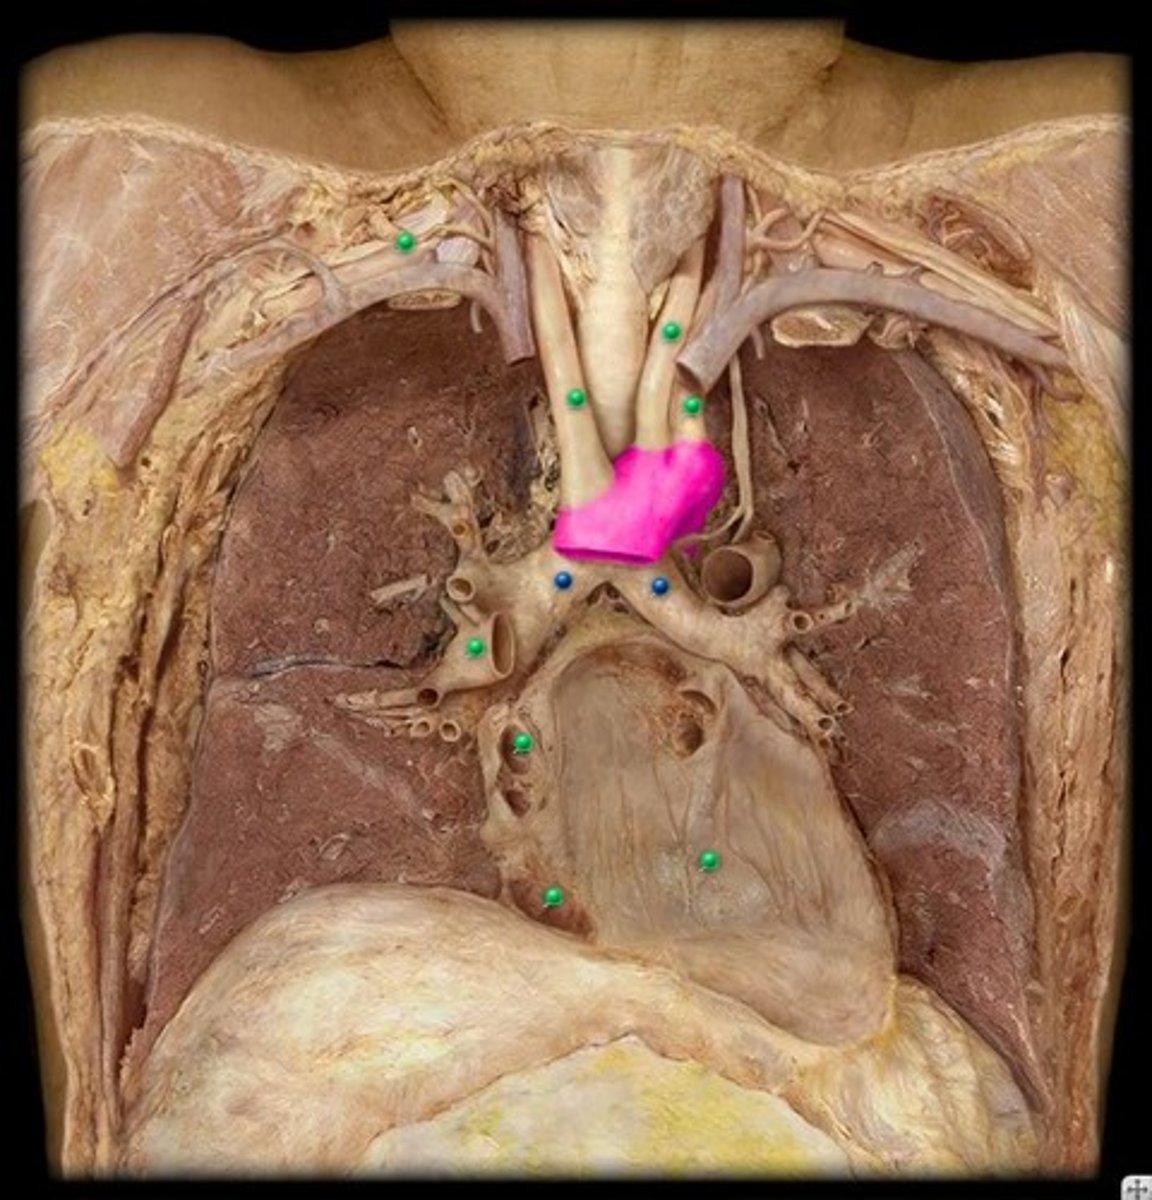

Thymus - Produces Immune hormones

Heart

Aortic arch - distributes from left ventricle to body

Pulmonary artery - deoxygenated blood to lungs

Diaphragm - respiration

Trachea - connects larynx to lungs

Lungs - respiration